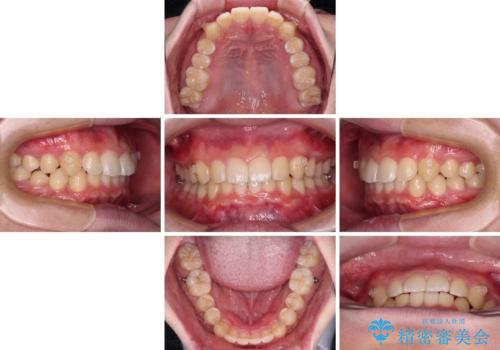

【モニター】斜めに突き出した前歯をインビザラインで改善

- 前方に傾斜した前歯を気にして来院された患者様です。

強く食いしばってしまう癖があり、下顎前歯に押し出されて上顎前歯が前方へ斜めに突き出している状態でした。

IPR(歯と歯の間を削る)を多用して、インビザラインにて矯正治療を行うこととしました。

口元を引っ込めるためのゴムかけを頑張っていただき、満足のいく上顎前歯の傾斜へ改善することができました。